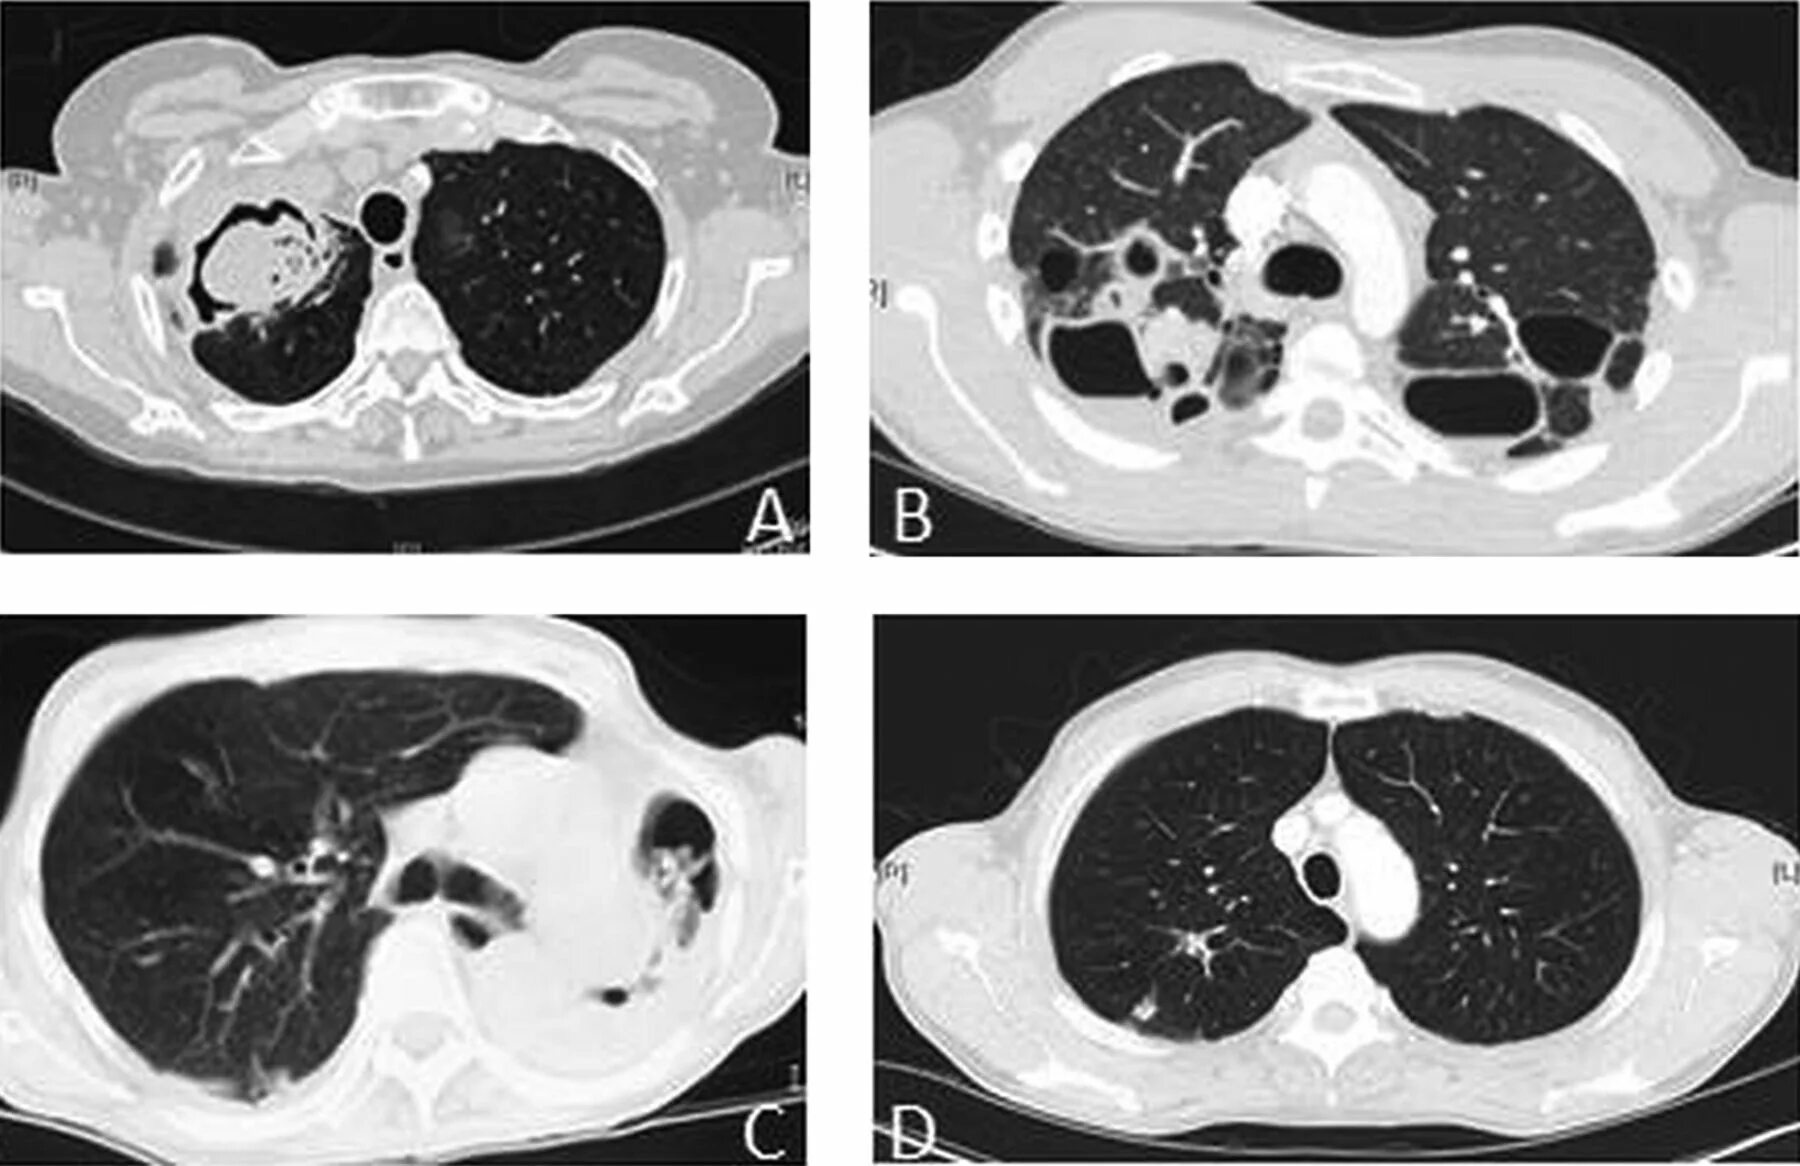

Болит кт